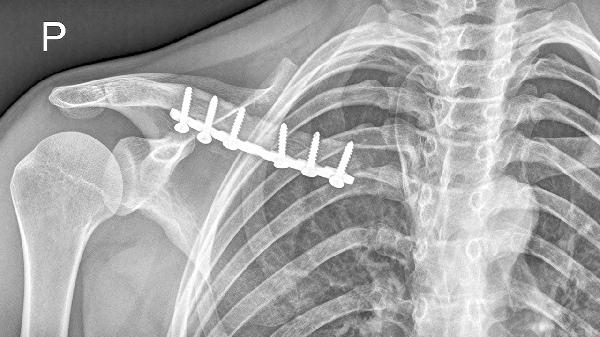

5、锁骨骨折愈合不良

锁骨骨折后若复位不佳或固定不牢固,可能形成畸形愈合。表现为骨折处骨痂过度增生或成角畸形,可能影响肩关节活动。陈旧性骨折畸形严重者可能需要截骨矫形手术,配合锁骨钢板内固定治疗。